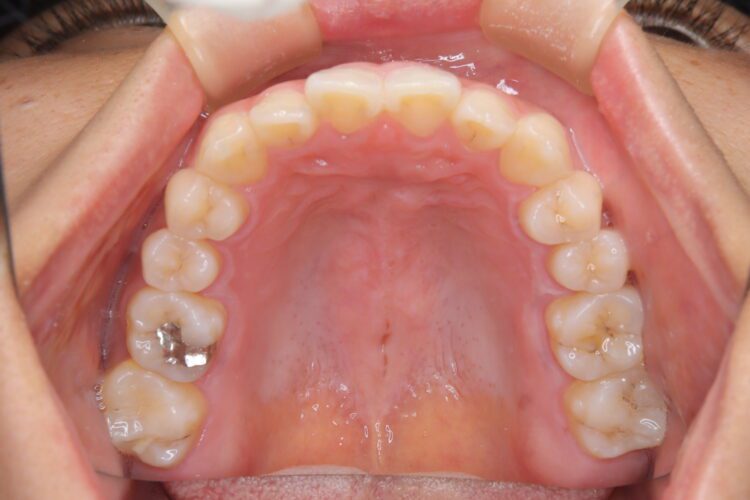

受け口の改善を主訴にご来院された患者様です。

軽度の下顎前突と診断し、マウスピース矯正装置(インビザライン)を用いて治療を行うこととしました。